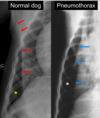

pneumothorax

Pneumothorax ● Skin folds – can mimic pneumothorax

pneumothorax cardiac silhouette looks lifted